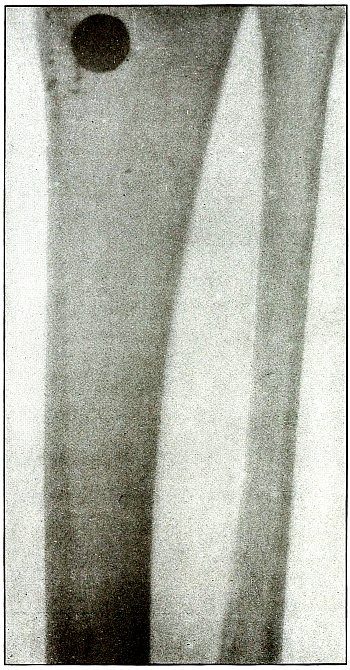

| 61. |

Gunshot fracture, tibia and fibula |

132 |

| 62. |